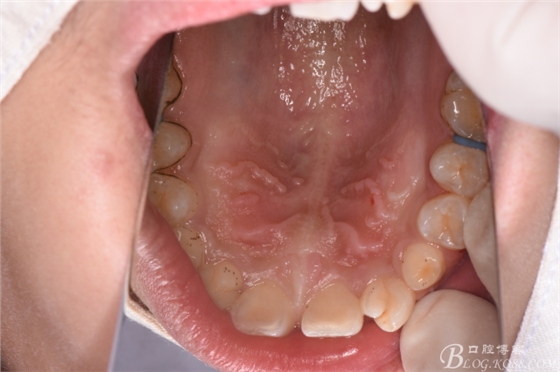

圖3.口內(nèi)觀:53、63滯留,13、23未見萌出

圖4.腭側(cè)觀:上顎平整、無(wú)明顯隆起,cbct準(zhǔn)確定位13、23位于腭側(cè)